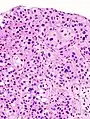

The 1973 WHO grading system for transitional cell carcinomas (papilloma, G1, G2 or G3) is most commonly used despite being superseded by the 2004 WHO[14] grading for papillary types (papillary neoplasm of low malignant potential [PNLMP], low grade, and high grade papillary carcinoma). High-grade carcinoma typically displays more pleomorphism, multiple mitoses, euchromatin and relatively prominent nucleoli, and uneven distribution of nuclei.

Transitional cell carcinoma, being low-grade to the left, and high-grade to the right. H&E stain